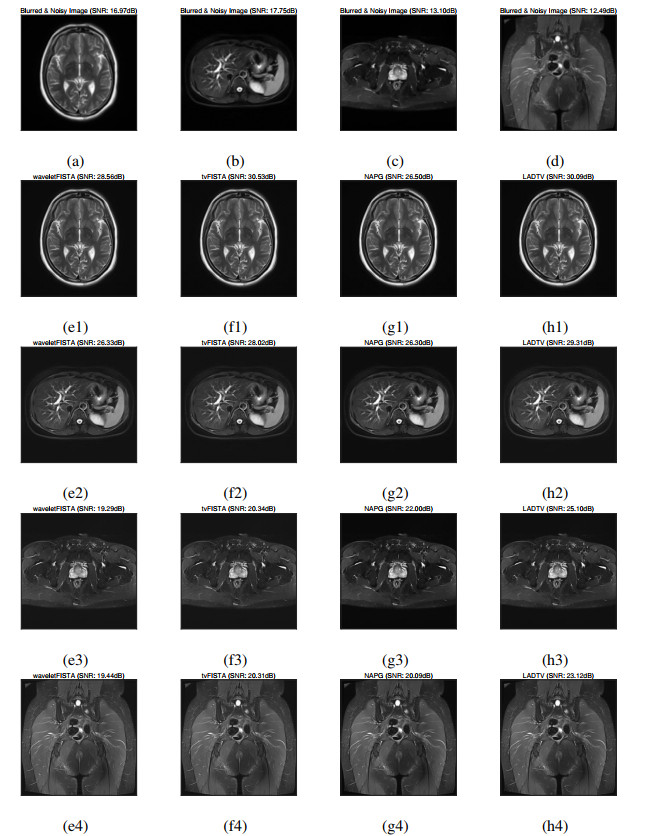

• This paper presents a magnetic resonance image deblurring and denoising model named the isotropic total variation regularized least absolute deviations measure (LADTV). More specifically, the least absolute deviations term is first adopted to measure the violation of the relation between the desired magnetic resonance image and the observed image, and to simultaneously suppress the noise that may corrupt the desired image. Then, in order to preserve the smoothness of the desired image, we introduce an isotropic total variation constraint, yielding the proposed restoration model LADTV. Finally, an alternating optimization algorithm is developed to solve the associated minimization problem. Comparative experiments on clinical data demonstrate the effectiveness of our approach to synchronously deblur and denoise magnetic resonance image.